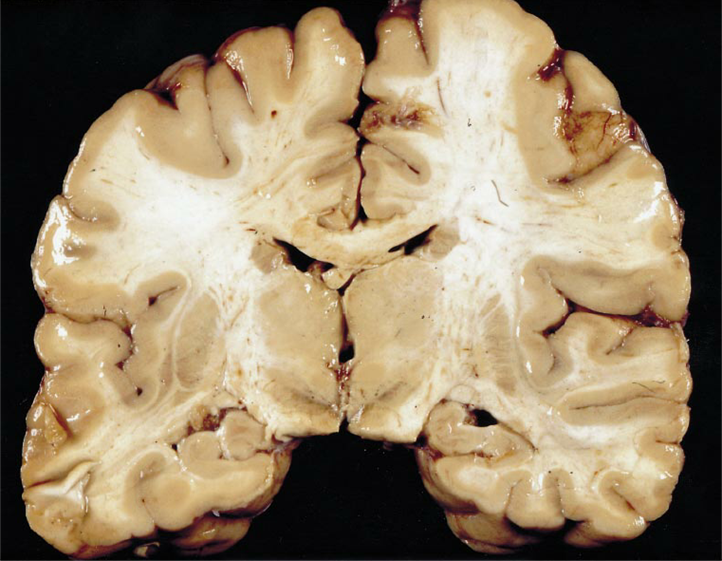

which plane is shown here?

coronal